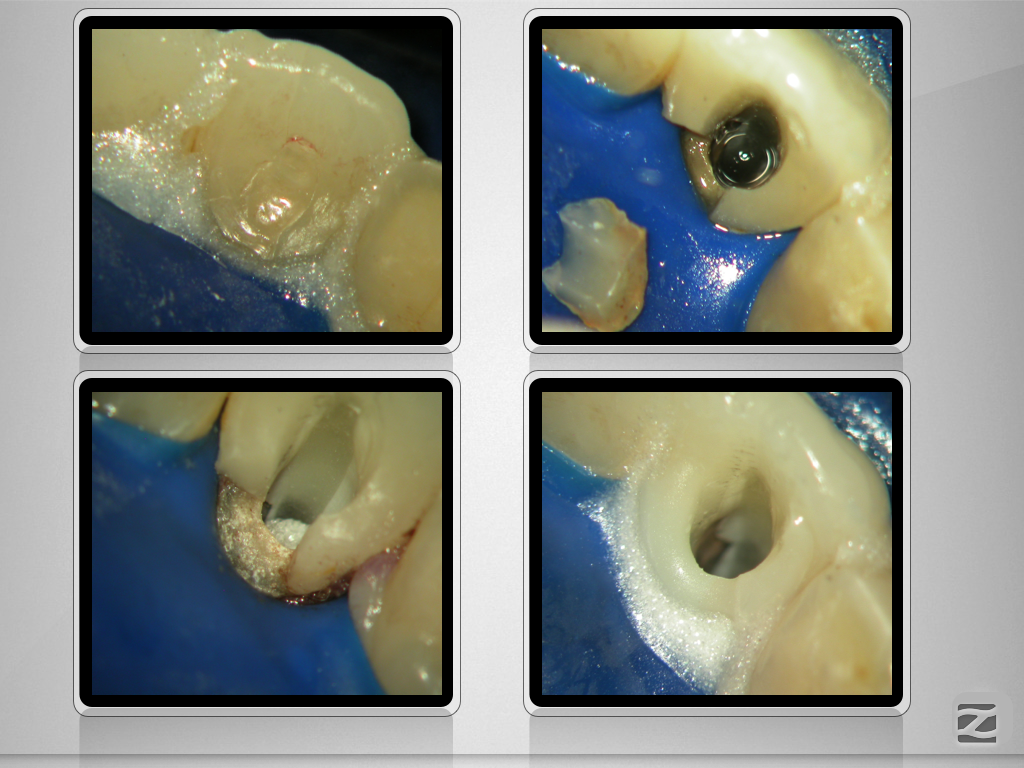

Kurioses Leakage